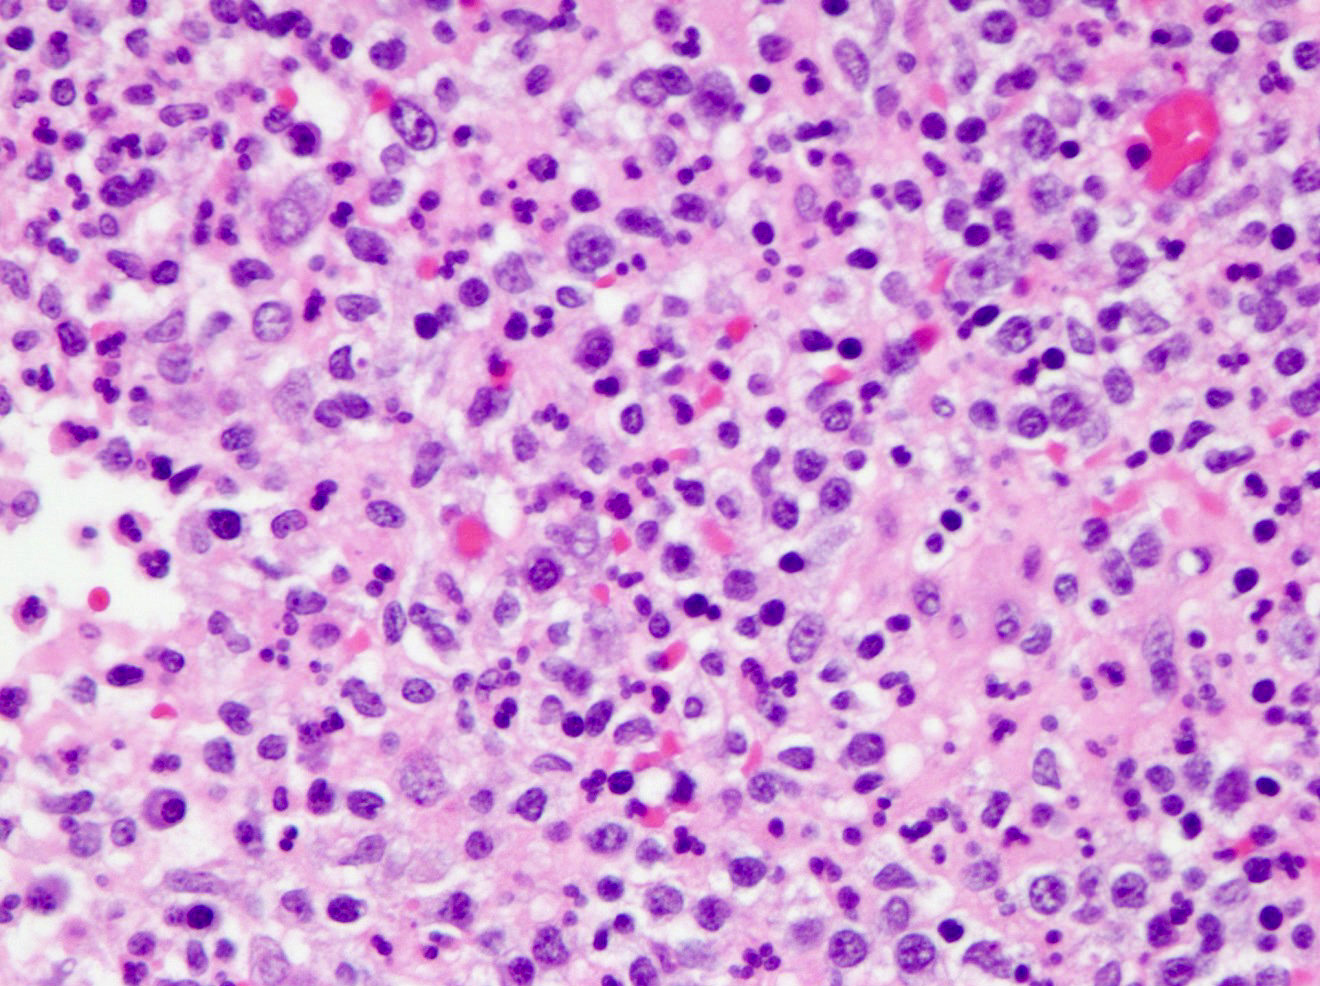

Microscopic (histologic) description

- Variable acute inflammation with predominance of neutrophils; involves some or all layers of the appendiceal wall

- Process may be divided into acute focal, acute suppurative, gangrenous and perforative

- Early lesions display mucosal erosions and scattered crypt abscesses

- Later, the inflammation extends into the lamina propria and collections of neutrophils are also seen in the lumen

- Mural necrosis in gangrenous appendicitis

- Process may be divided into acute focal, acute suppurative, gangrenous and perforative

Microscopic (histologic) images

A 40 year old caucasian man presented into the emergency room with right lower quadrant pain associated with vomiting, abdominal tenderness, fever and moderate leukocytosis. Acute appendicitis was suspected and he underwent an appendectomy. His appendix was sent to pathology for histological evaluation. The H&E images are shown above. Which of the following is the most likely diagnosis?